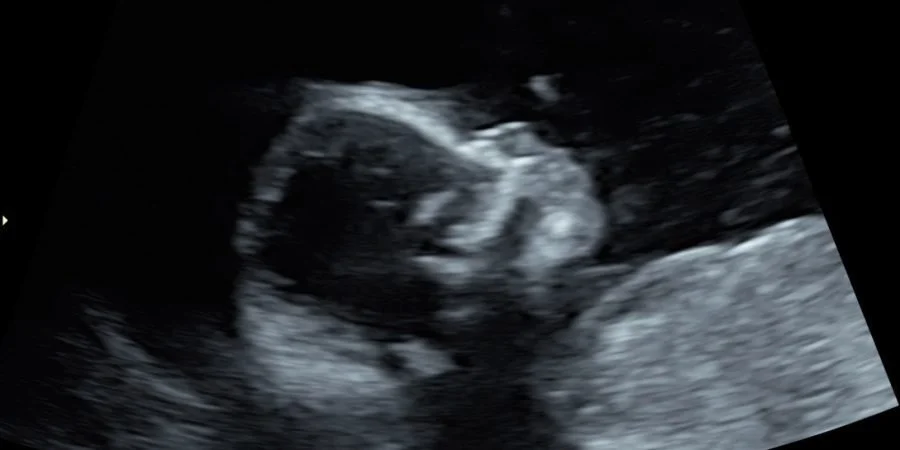

I recently had my 18-week anatomy scan. The good news: my cervix was still closed and measuring the same as it was two weeks ago. We also got to see our baby again, which was such a blessing.

This mid-pregnancy scan is done to ensure that the baby is growing properly and that there are no organ deformities. Our baby looked healthy and right on track, but we do have to go back in a week because our little one decided to have a field day in my belly and wouldn’t sit still for the sonographer.

All in all, our baby is healthy and growing just as expected.